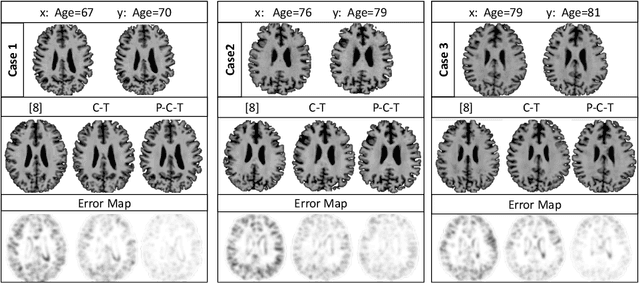

Abstract:Simulating images representative of neurodegenerative diseases is important for predicting patient outcomes and for validation of computational models of disease progression. This capability is valuable for secondary prevention clinical trials where outcomes and screening criteria involve neuroimaging. Traditional computational methods are limited by imposing a parametric model for atrophy and are extremely resource-demanding. Recent advances in deep learning have yielded data-driven models for longitudinal studies (e.g., face ageing) that are capable of generating synthetic images in real-time. Similar solutions can be used to model trajectories of atrophy in the brain, although new challenges need to be addressed to ensure accurate disease progression modelling. Here we propose Degenerative Adversarial NeuroImage Net (DaniNet) --- a new deep learning approach that learns to emulate the effect of neurodegeneration on MRI. DaniNet uses an underlying set of Support Vector Regressors (SVRs) trained to capture the patterns of regional intensity changes that accompany disease progression. DaniNet produces whole output images, consisting of 2D-MRI slices that are constrained to match regional predictions from the SVRs. DaniNet is also able to condition the progression on non-imaging characteristics (age, diagnosis, etc.) while it maintains the unique brain morphology of individuals. Adversarial training ensures realistic brain images and smooth temporal progression. We train our model using 9652 T1-weighted (longitudinal) MRI extracted from the Alzheimer's Disease Neuroimaging Initiative (ADNI) dataset. We perform quantitative and qualitative evaluations on a separate test set of 1283 images (also from ADNI) demonstrating the ability of DaniNet to produce accurate and convincing synthetic images that emulate disease progression.